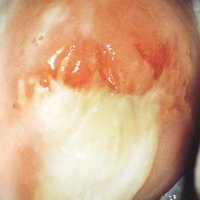

Але іноді відбуваються ускладнення і процес загоєння затягується з'явилися хворобами. Таким явищем може стати поява яскраво жовтих, хворобливих виділень вже на 4-5 день. Причиною цього стає ендометрит - запалення поверхні слизової оболонки матки. Як правило, такі виділення супроводжує вкрай неприємний запах гнилі, виділення мають слизовий вигляд.

Також жовтуваті лохії можуть з'являтися через великих шматків посліду, це створює закупорку і накопичення, проблемою можуть стати рясні згустки крові, це не дозволяє пройти посліду через матку. У підсумку зібралася слиз і згустки починають загнивати, відбувається запальний процес слизової оболонки.

Через сильну травми піхви або слизової матки, на місцях розриву можуть утворитися нагноєння і привести до інфекції і запалення.

Якщо відбулося інфікування всередині після пологів або ж інфекція змогла проникнути зовні під час пологів, то так чи інакше вона переходить в запальний процес всередині матки. Це викликано тим, що імунітет жінки після пологів вкрай слабкий.

Оптимально, якщо жінка зверне на це увагу ще в початковій стадії, коли виділення тільки з'явилися. Гірше, коли вже з'явилася температура, а також різкі болі внизу живота. Тут потрібен медичний догляд, ендометрит лікувати самостійно неможливо, необхідно обстеження і діагноз. Чим довше йде затримка або спроби вилікуватися самостійно, тим гірше можуть бути наслідки.

Початкова стадія запального процесу обходиться курсом антибіотиків і при потребі може бути призначена фізіотерапія.

Набагато гірше, якщо запалення поширилося по матці, як правило, це вимагає вискоблювання матки. При цьому видаляється шар ендометрія, а також все, що міститься в матці, а нижній шар з часом відновлюється. Операція робиться під загальною або місцевою анестезією.

Гнійні виділення після пологів

Гнійні виділення після пологів можуть з'явитися через розвинутої інфекції. Найчастіше інфекція розвивається в області тазу або черевної порожнини. Вони можуть виникнути через кілька днів і через місяць. При перших симптомах потрібно звернутися до фахівця.